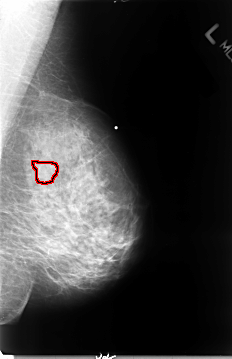

B_3072_1.RIGHT_CC

LEFT_MLO LINES 4656 PIXELS_PER_LINE 3016 BITS_PER_PIXEL 12 RESOLUTION 50 OVERLAY

FILE: B_3072_1.LEFT_CC.OVERLAY

TOTAL_ABNORMALITIES 1

ABNORMALITY 1

LESION_TYPE MASS SHAPE IRREGULAR MARGINS OBSCURED-ILL_DEFINED

ASSESSMENT 3

SUBTLETY 3

PATHOLOGY MALIGNANT

TOTAL_OUTLINES 1

BOUNDARY